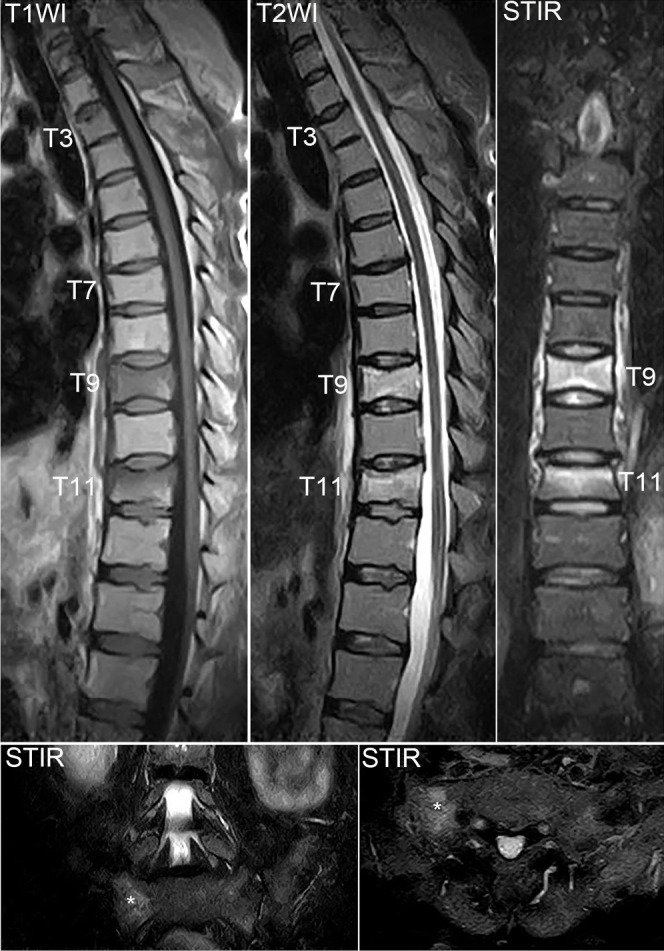

背景:妊娠和哺乳期相关骨质疏松症(PLO)是一种罕见的影响妊娠晚期和哺乳期早期妇女骨骼脆弱的疾病。PLO患者经历多发、快速发作的椎体骨折并发展为后凸,当诊断和治疗延迟时,预后较差。由于没有针对PLO患者的标准治疗方案,治疗应单独计划。近年来,romosozumab已被公认为治疗严重骨质疏松症患者最有效的药物之一。因为它可以在短时间内显著增加绝经后骨质疏松症妇女的骨密度(BMD),它对治疗骨质疏松症进展迅速且骨折风险高的患者是有用的。在这里,我们报告一例PLO合并多椎体骨折用romosozumab治疗。据我们所知,这是首个单独使用romosozumab治疗PLO的报道。病例描述:一名中年产后和哺乳期妇女在怀孕9个月时背部疼痛,分娩后恶化。PLO的诊断基于多发胸椎和骶骨脆性骨折和低骨密度。她接受罗莫索单抗治疗,背部疼痛逐渐消退。经过12个月的罗莫索单抗治疗,她的腰椎骨密度比基线增加了22.1%,并且没有发生进一步的骨折。结论:12个月的romosozumab治疗成功改善了重症PLO患者的临床状况,BMD显著增加。

Case description: A middle-aged postpartum and lactating woman experienced back pain at 9 months of pregnancy, which worsened after delivery. PLO was diagnosed based on multiple thoracic vertebral and sacral fragility fractures and low BMD. She was treated with romosozumab, and her back pain gradually subsided. After 12 months of romosozumab treatment, her lumbar spine BMD increased by 22.1% from baseline, and no further fractures occurred.